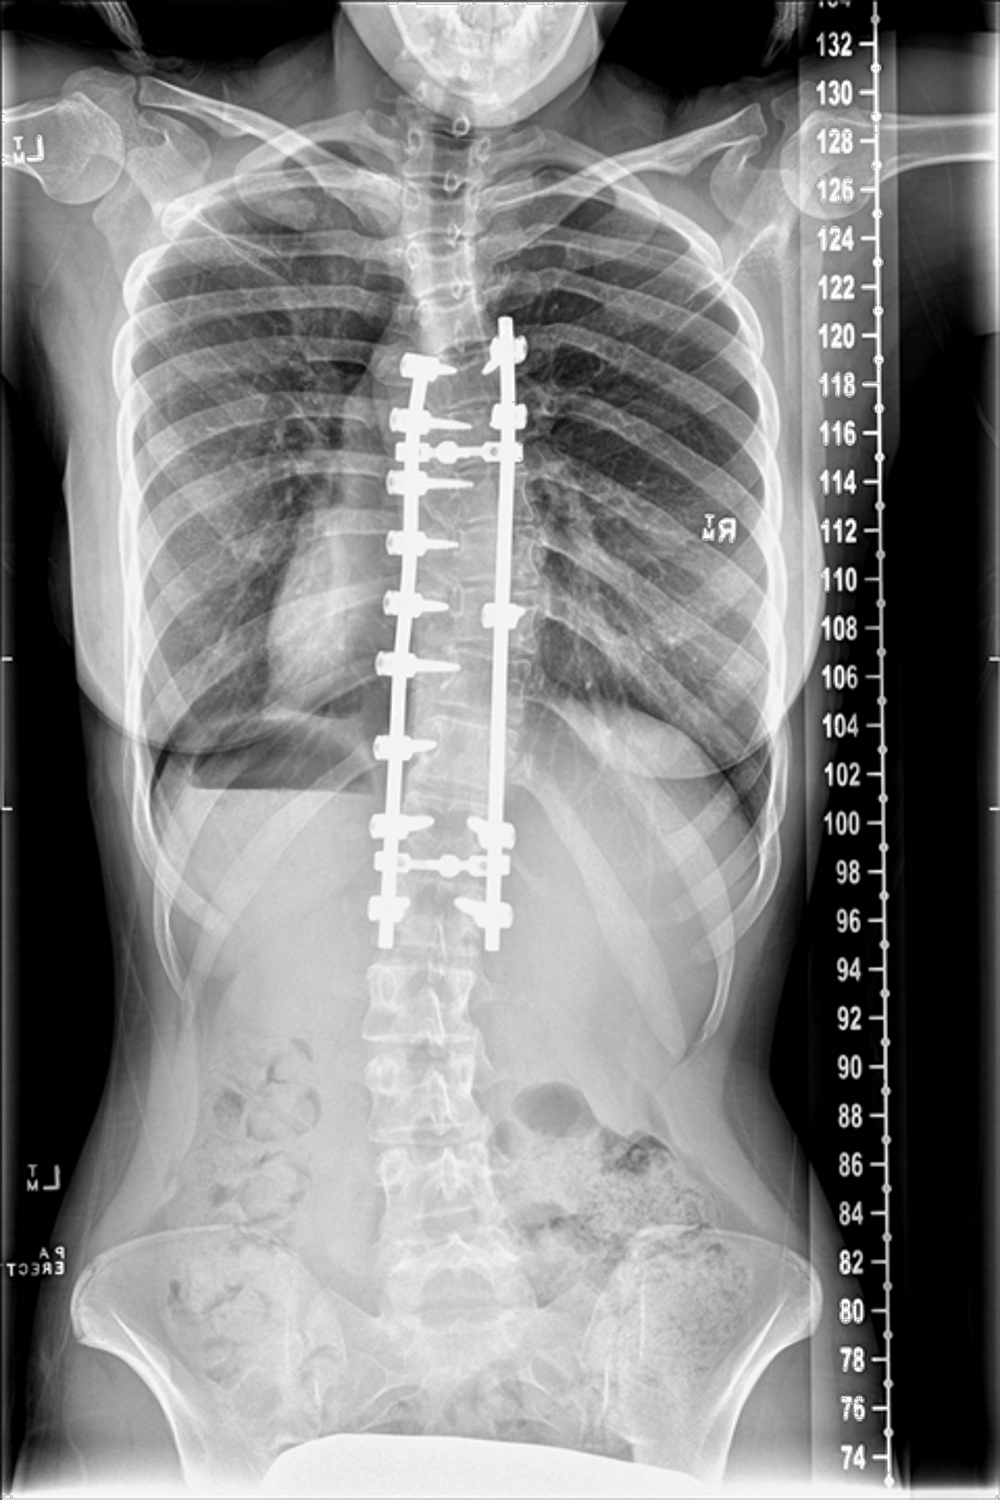

Below is a comparison of before and after images and x-rays of a teenager who underwent surgery due to her scoliosis:

After |

|

![]() |